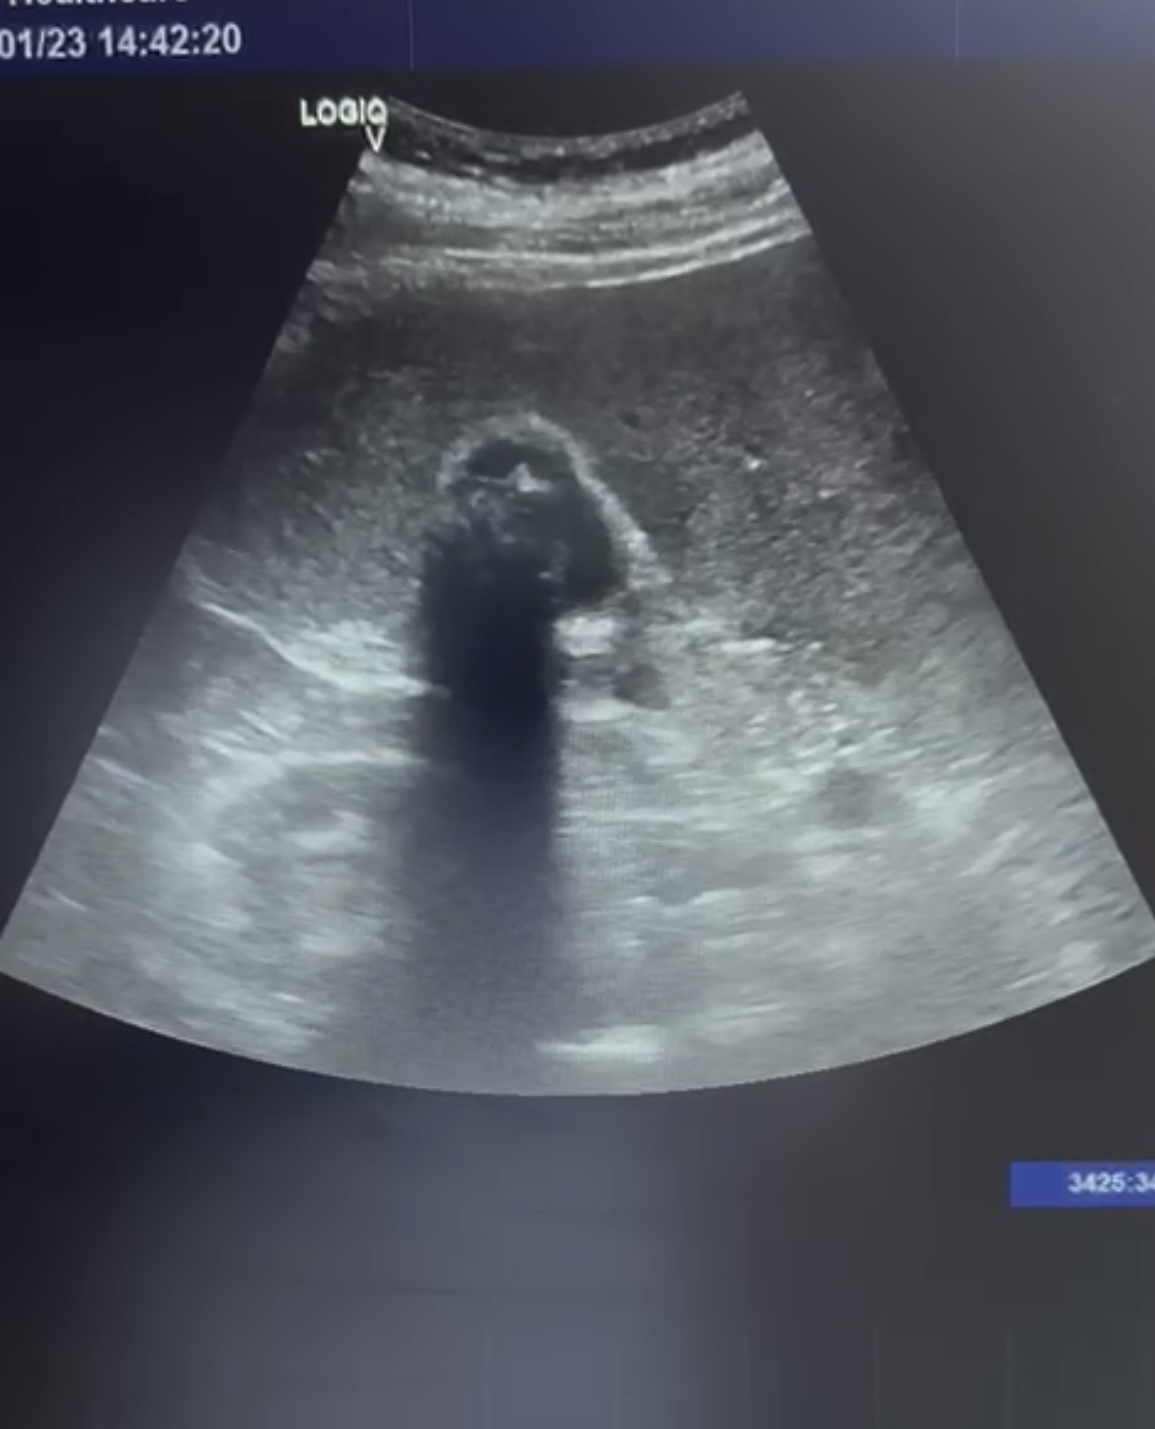

Hallazgos ecográficos

Se observa la vesícula biliar con varias litiasis en su interior y sombra acústica posterior. No se observan signos de colecistitis ni dilatacion de la vía biliar.